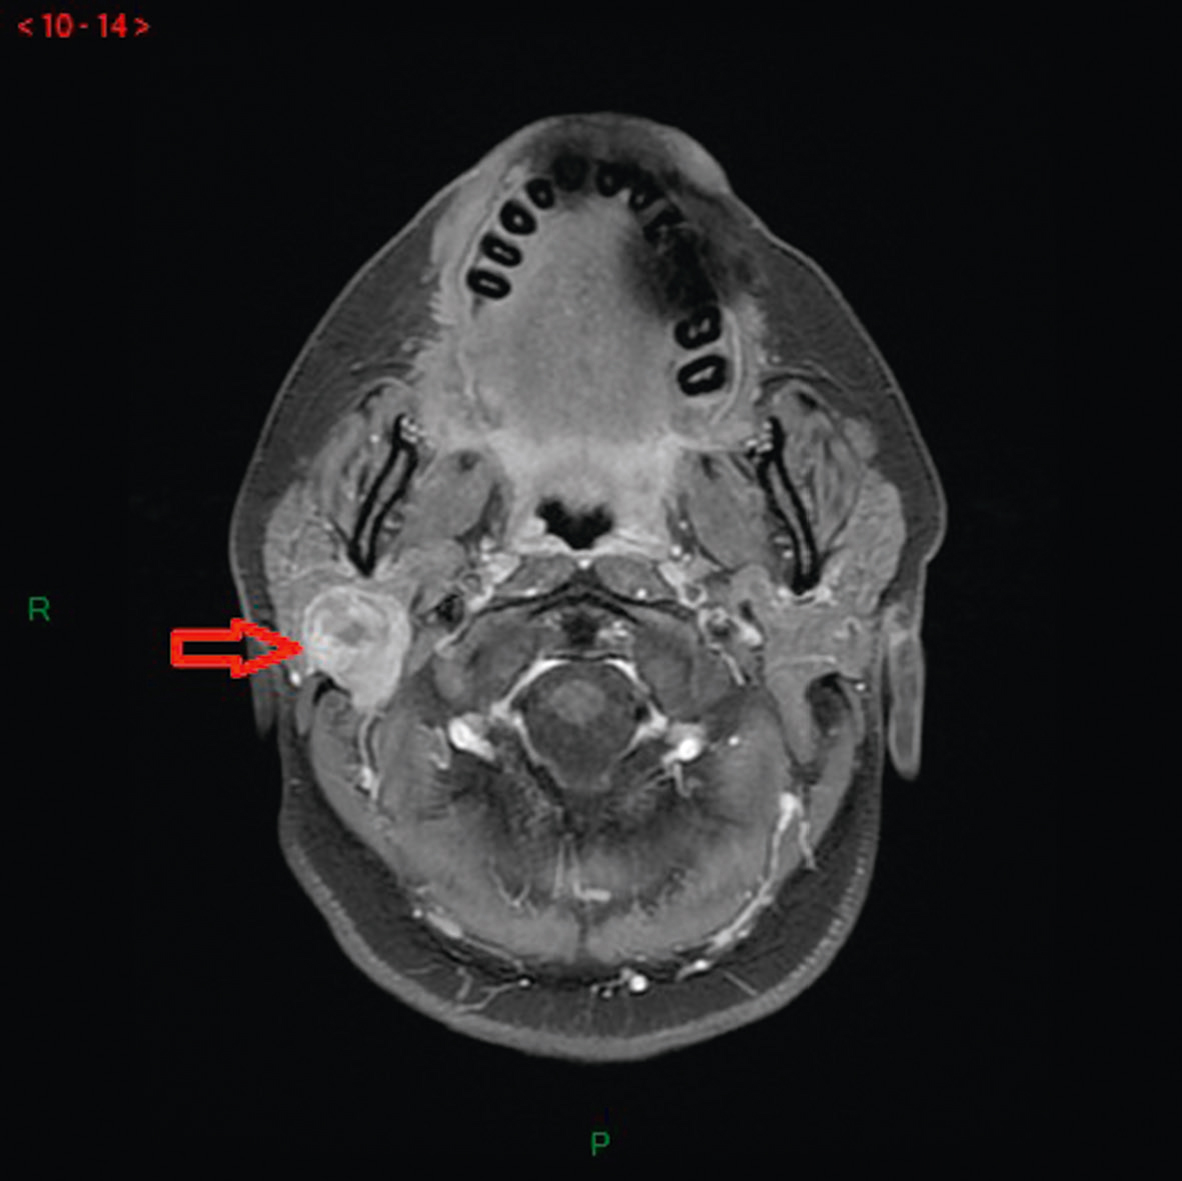

• Autre : scanner/IRM cervicaux avec injection, en cas de tuméfaction homolatérale à la paralysie faciale, à la recherche d’une parotidite ou d’une tumeur parotidienne (fig. 12.3).

Fig. 12.3

IRM cervicale, séquence T1 avec injection de gadolinium.

Tumeur parotidienne droite (flèche) compliquée d’une paralysie faciale périphérique. Source : courtoisie du Dr E. Sauvaget, ORL.L'image montre une IRM cervicale en séquence T1 avec injection de gadolinium. L'IRM, ou imagerie par résonance magnétique, utilise des champs magnétiques et des ondes radio pour créer des images détaillées des structures internes du corps. La séquence T1 est un type de séquence d'IRM qui offre une bonne résolution spatiale et un contraste entre les structures anatomiques. L'injection de gadolinium, un agent de contraste, améliore la visibilité des vaisseaux sanguins, des tumeurs et des zones d'inflammation. Sur cette image, on voit une coupe transversale de la région cervicale, c'est-à-dire la partie du cou contenant la colonne vertébrale cervicale, les muscles, les vaisseaux sanguins et les nerfs. Une flèche rouge pointe vers une zone spécifique, indiquant probablement une anomalie ou une structure d'intérêt particulier. Cette image permet de visualiser des détails importants de la région cervicale, aidant ainsi les professionnels de santé à diagnostiquer et à planifier des traitements appropriés.

- • 225Dans un contexte de paralysie faciale supposée idiopathique, il est discuté de réaliser une IRM avec injection de gadolinium, étudiant tout le trajet du nerf facial sans oublier la portion parotidienne, si possible au cours du premier mois. Cette IRM apporte des arguments en faveur du diagnostic positif et élimine une pathologie tumorale. Elle doit être systématique face à toute atypie lors de l’examen clinique.